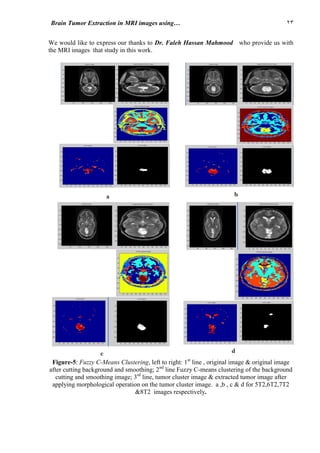

10.4 K-Means Clustering Based on the Centers’ values of the clusters of Fuzzy C-Means

algorithm

In this adaptive technique, Fuzzy C-Means (FCM) clustering algorithm was implemented on

the input MRIs (six clusters). The segmented image with center values of the clusters then

passed to the K-Means clustering algorithm (with also six clusters), the resulted image then

segmented. The image of the cluster of the tumor is selected by applying the opening

morphological operation with structure element of disk shape (four pixels diameter size), the

images 5T2,6T2,7T2 and (three pixels diameter size) for 8T2 image, then convoluted with the

original image to obtain the image of the tumor region, shown in fig.6. The tumor region

surface area is given Table-1.

Figure-6: K-Means Clustering based on the centers’ values of the clusters of Fuzzy C-Means

algorithm, left to right: 1st

line, original image & original image after cutting background and

smoothing ; 2nd

line, Fuzzy C-means clustering of the background cutting and smoothing

image & K-means clustering of the background cutting and smoothing image based on

clusters' centers values of FCM algorithm; 3rd

line, tumor cluster image & extracted tumor

image after applying morphological operation on the tumor cluster image . a, b, c& d for 5T2,

6T2, 7T2 & 8T2 images respectively. .

c